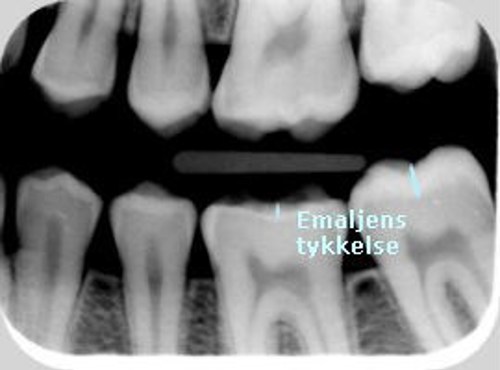

På røntgenbilledet ses en kindtand, hvor emaljen næsten er ætset væk. Hvor tyk emaljen skulle have været, kan ses på nabotanden.